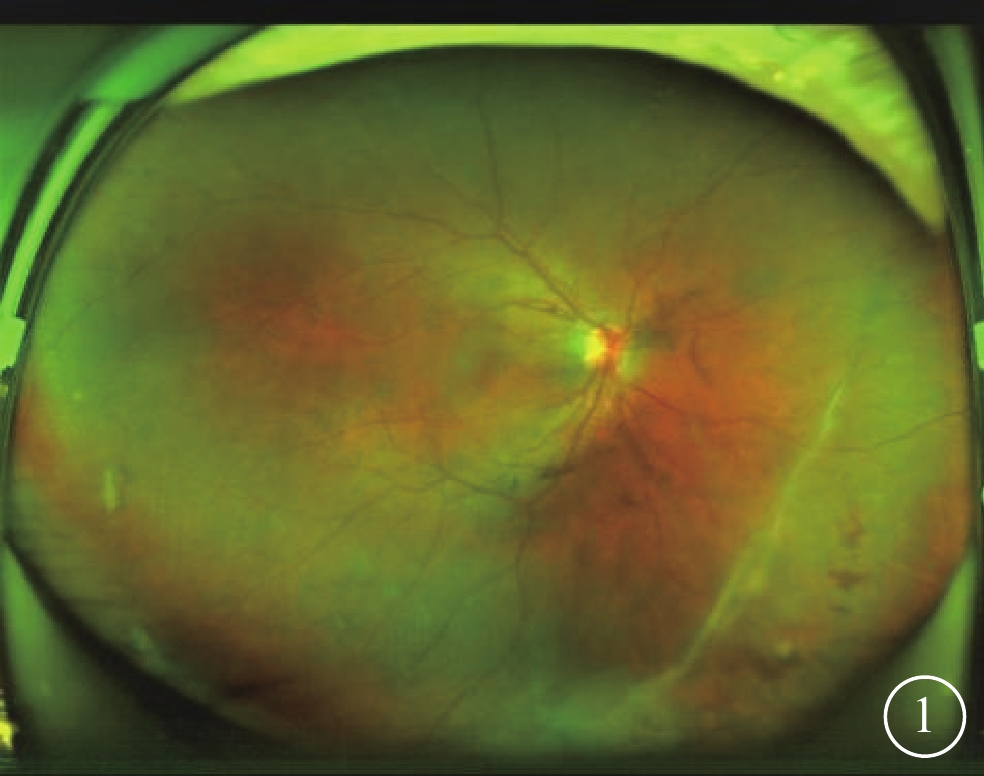

患者男,27歲。因右眼反復視力下降、視物變形2年余2020年11月2日在合肥愛爾眼科醫院就診。患者既往身體健康,犬類密切接觸史2年。2年前在當地醫院診斷為“葡萄膜炎、黃斑水腫、玻璃體積血”,初次使用糖皮質激素(以下簡稱為激素)療效明顯,但病情頻繁反復,后續使用激素效果不佳。眼科檢查:右眼視力0.25,矯正不能提高;左眼視力1.0。右眼、左眼眼壓分別為18、12 mm Hg(1 mm Hg=0.133 kPa)。雙眼眼前節未見明顯異常。右眼玻璃體腔混濁伴積血條索,鼻下及顳下象限周邊玻璃體見灰白色團塊樣混濁。激光掃描檢眼鏡檢查,右眼視盤輕度充血、水腫,2:00至6:30時鐘位周邊視網膜見增生條索,其上視網膜皺褶、血管紆曲,黃斑中心蜂窩狀隆起,中心凹反光消失,鼻下周邊視網膜見出血點(圖1)。光相干斷層掃描血管成像(OCTA)檢查,右眼后極部毛細血管密度降低,黃斑區拱環擴大不規則(圖2);B掃描像顯示中心凹處視網膜神經上皮層隆起,視網膜神經上皮層增厚呈山峰狀,外叢狀層內可見多個大小不等的囊腔,囊腔內呈弱反射信號(圖3)。B型超聲檢查,右眼玻璃體混濁呈分層強回聲,鼻下象限局部視網膜輕度隆起(圖4)。左眼眼底、OCTA及B型超聲檢查均未見異常。患者拒絕行熒光素眼底血管造影檢查。診斷:右眼黃斑囊樣水腫(CME)、右眼玻璃體積血、右眼牽拉性視網膜脫離,右眼弓蛔蟲病?患者于2020年11月3日行玻璃體切割聯合增生膜剝離手術,手術中取患眼玻璃體腔及前房液體樣本送檢;剝離鼻下象限視網膜表面增生條索,在皺褶視網膜邊緣行532 nm激光光凝治療,并于玻璃體腔注入0.05 ml(2 mg)曲安奈德注射液。眼內液及血清檢測結果顯示:血清弓蛔蟲IgG 38.66 U(參考值<9 U),眼內液弓蛔蟲IgG 4.96 U(參考值<3 U),Glodmann-Witmer系數4.13(參考值<2 U)。明確診斷:右眼弓蛔蟲病。手術后口服醋酸潑尼松片30 mg/d,持續14 d;阿苯達唑片400 mg/次,隔月1次,共2次。患者于出院后2個月復查,病情無反復,自訴視物變形癥狀消失。右眼視力0.8,眼壓19 mm Hg;玻璃體腔清亮;視盤無明顯充血水腫,視網膜平復,黃斑水腫消失;OCTA檢查可見視網膜層次結構完整。